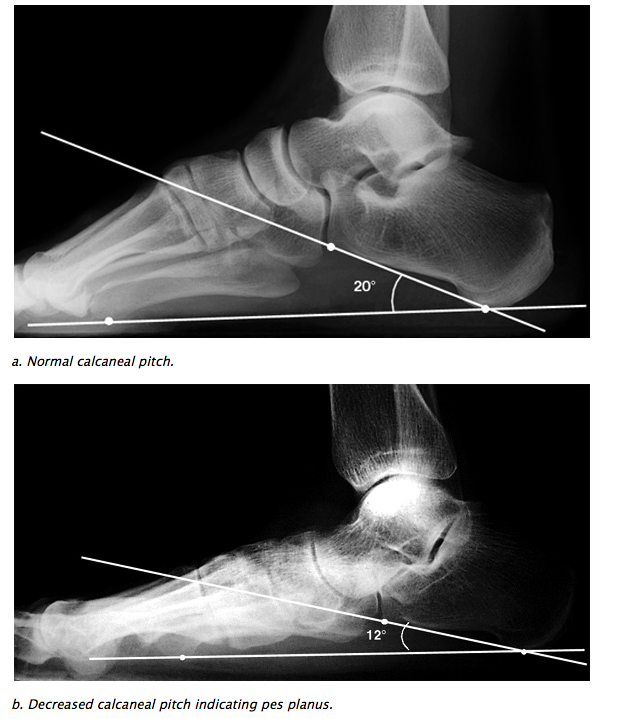

COLLAPSE OF LONGITUDINAL ARCH

• Lateral: 1st metatarsal talar angle

• Lateral: Calcaneal pitch